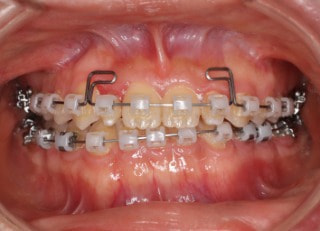

治療開始時

治療開始から25ヶ月後